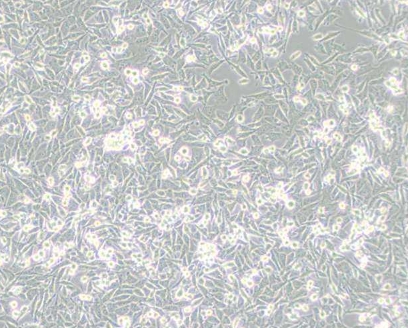

2. 细胞名称:PaTu 8988t(人胰腺癌细胞)

8. 细胞类型:上皮细胞样

9. 生长特性:贴壁生长

1. 背景特征:来源于原发性胰腺癌肝转移组织;具有姐妹细胞系PA-TU-8988S(DSM ACC 204);典型的上皮细胞形态。

2. 生长特性:倍增时间:22-30小时;贴壁生长,形态规则;增殖活性稳定。